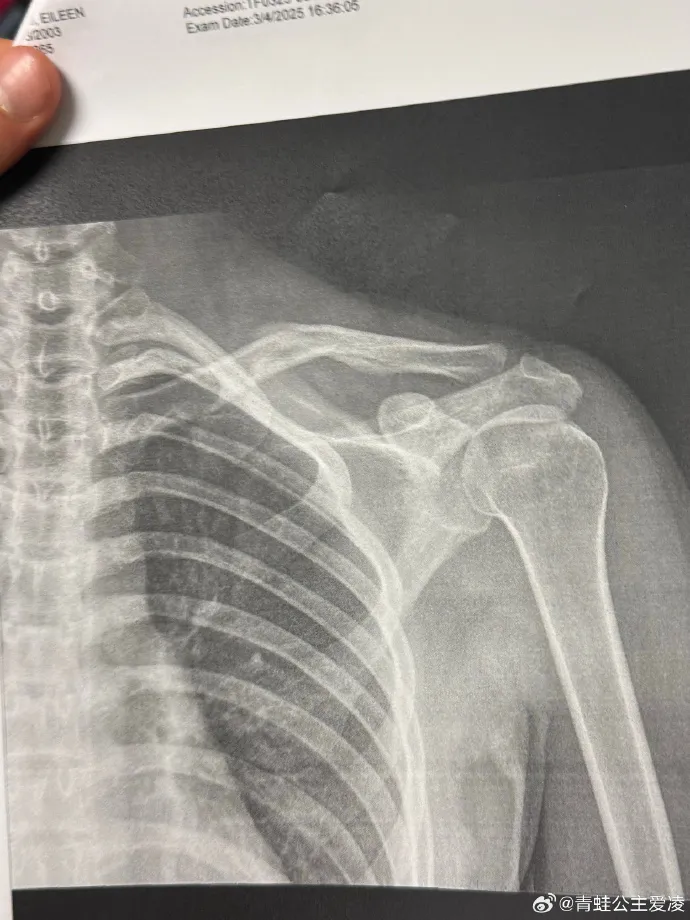

3月,她在社交平台公布了锁骨骨折的X光影像。经过数月休养,她于8月重返雪场训练,不料再遇“人为事故”导致受伤。

今年3月9日,谷爱凌在社交媒体晒出肩部骨折的X光照片,并配上一个心碎的表情,随后相关话题登上热搜。